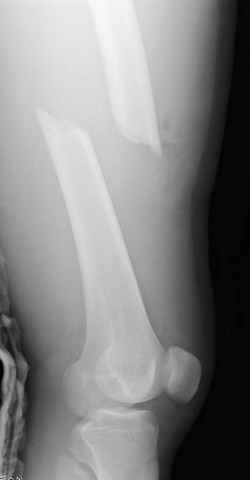

больному 42, автоавария, политравма, открытая черепномозговая травма, безсознании, открытый перелом бедра, размозжение мягких тканей, дефект кожи на передней поверхности бедра около 13 см2 от ожога, компартмент синдром.

По поводу открытого перелома больной ургентно взят на ретроградное интрамедулярное штифтование, после рутинного дебрайдмента и фасциотомии на бедре и на голени.

перелом бедра

интраоперационные

постоперационные